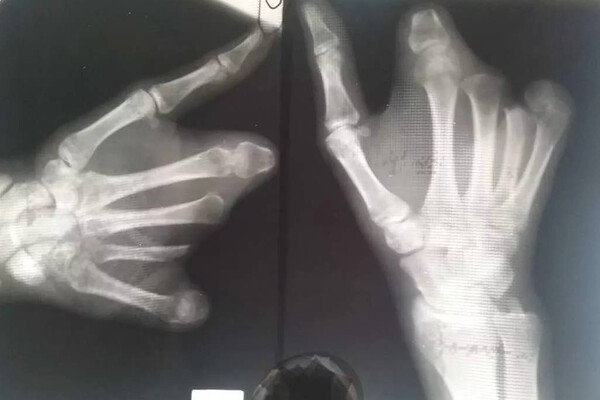

«Несовершеннолетний поступил в больницу с пиротехнической травмой, контузией левого глаза, ссадинами лица и раной левой кисти», — рассказали полицейские.